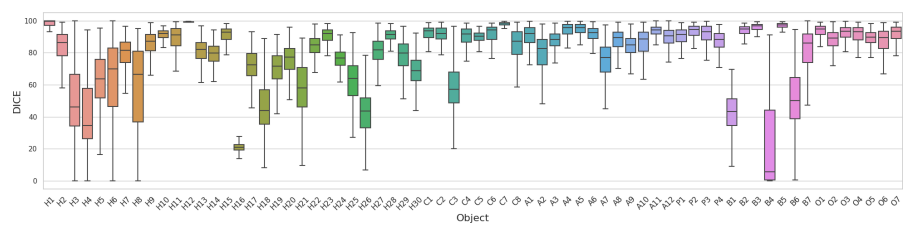

本研究全面地评估了SAM的各种模式在大规模、多样化的医学影像数据集上的分割性能,DICE指标评估结果如图4所示。

图4 不同测试策略的DICE箱线图。从上到下:S1H、S2、S3、S4、S5、S6。